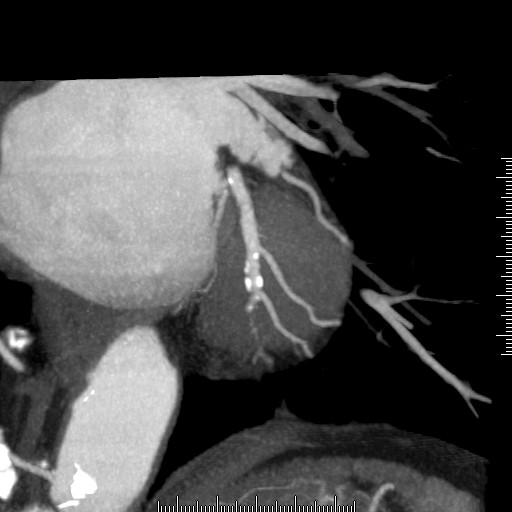

冠状動脈バイパス手術後の経過観

手術後の患者様の経過を下記の通り観察できます。心臓の裏側ももちろん診断可能です。

様々な画像表示処理方法を用い診断します。

ボリュームレンダリング